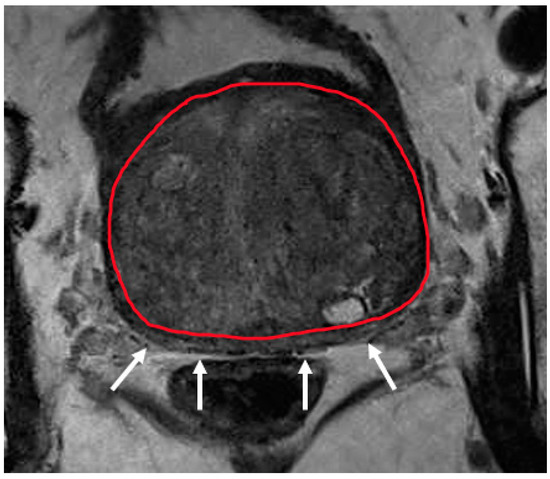

2.5.1. EPE Prediction